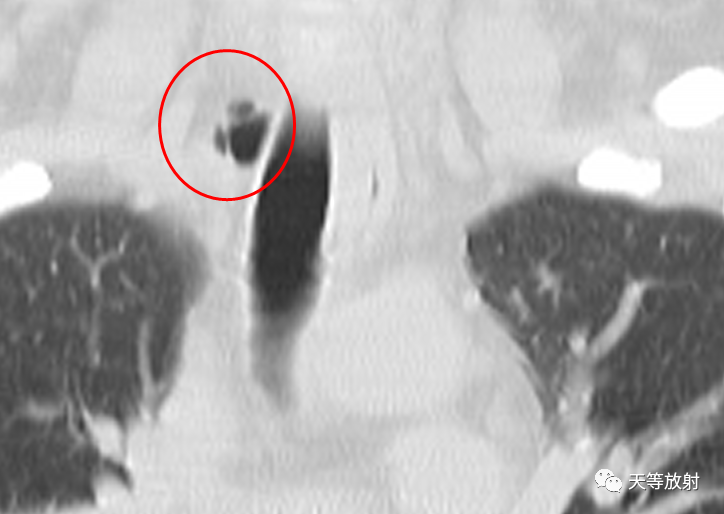

冠状位及矢状位观察,囊影位于胸廓入口右侧旁。